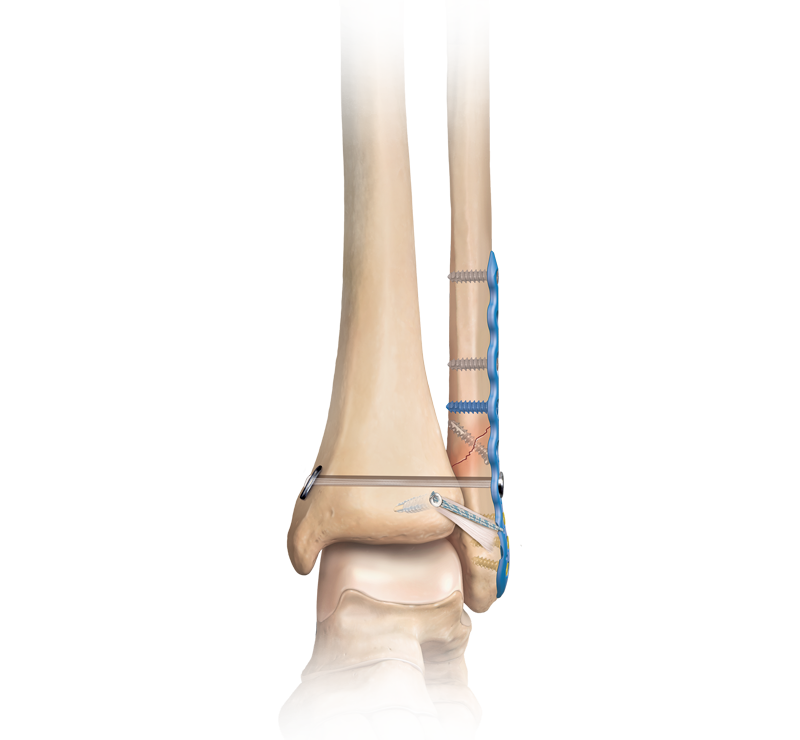

O.R.I.F. is an abbreviation for Open Reduction Internal Fixation. Open reduction internal fixation is a method of surgically repairing a fractured bone. Generally, this involves either the use of plates and screws or an intramedullary (IM) rod to stabilize the bone.

An open reduction and internal fixation (ORIF) is a type of surgery used to fix broken bones. This is a two-part surgery. First, the broken bone is reduced or put back into place. Next, an internal fixation device is placed on the bone; this can be screws, plates, rods, or pins used to hold the broken bone together.

This surgery is done to repair fractures that would not heal correctly with casting or splinting alone:

- Failure of closed reduction and pecutaneous pin fixation;

- Fractures presenting more than 2 mm of displacement and greater than 15 deg of talometatarsal angulation);